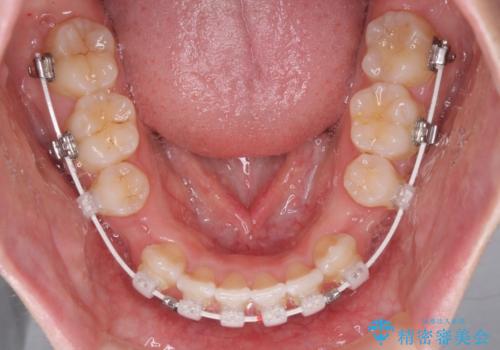

- 矯正装置

- 審美装置

- 1年11ヶ月

- 10-30回